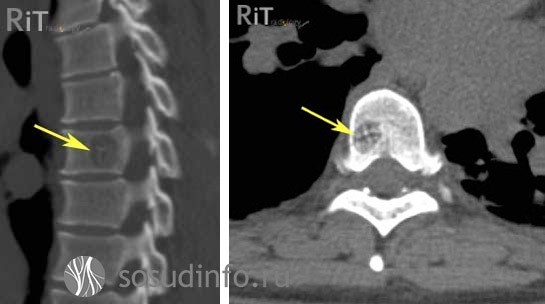

Для поиска гемангиомы тела позвонка используют:

- Обзорную рентгеновскую спондилографию, выявляющую структурные изменения в пораженном позвонке;

- Довольно информативную в этом плане компьютерную томографию (КТ);

- Значительные надежды при диагностике опухоли возлагают на магнитно-резонансную томографию (МРТ) – этот метод предоставляет наибольший объем информации в отношении патологического процесса.

гемангиома позвоночника на рентгеновском снимке